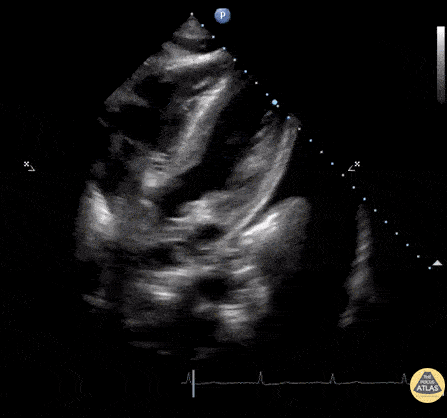

Subcostal window of patient with Lupus. An anechoic region is seen within the peritoneum, pericardium, and left lung indicating simultaneous ascites, pericardial effusion, and pleural effusion respectively. Image courtesy of Robert Jones DO, FACEP @RJonesSonoEM Director, Emergency Ultrasound; MetroHealth Medical Center; Professor, Case Western Reserve Medical School, Cleveland, OH View his original post here